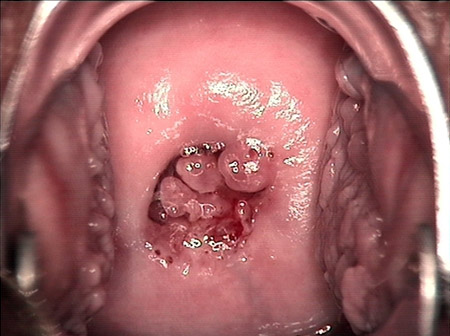

婦科leep錐切手術(shù) CIN2-3

CIN 2-3

CIN 2-3 碘著色后

CIN 2-3 leep術(shù)后

CIN 2-3 修復(fù)后

CIN 2-3 修復(fù)后(圖2)